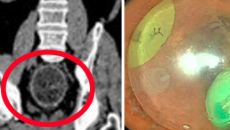

항문에 6.5cm 공 넣은 60대…의료진 '기발한' 아이디어로 제거

[스포츠조선 장종호 기자] 중국의 60대 남성이 항문에 장난감 공이 끼어 병원에서 제거 시술을 받았다. 중국 광동성 렌저우 인- 2025-04-24 08:50